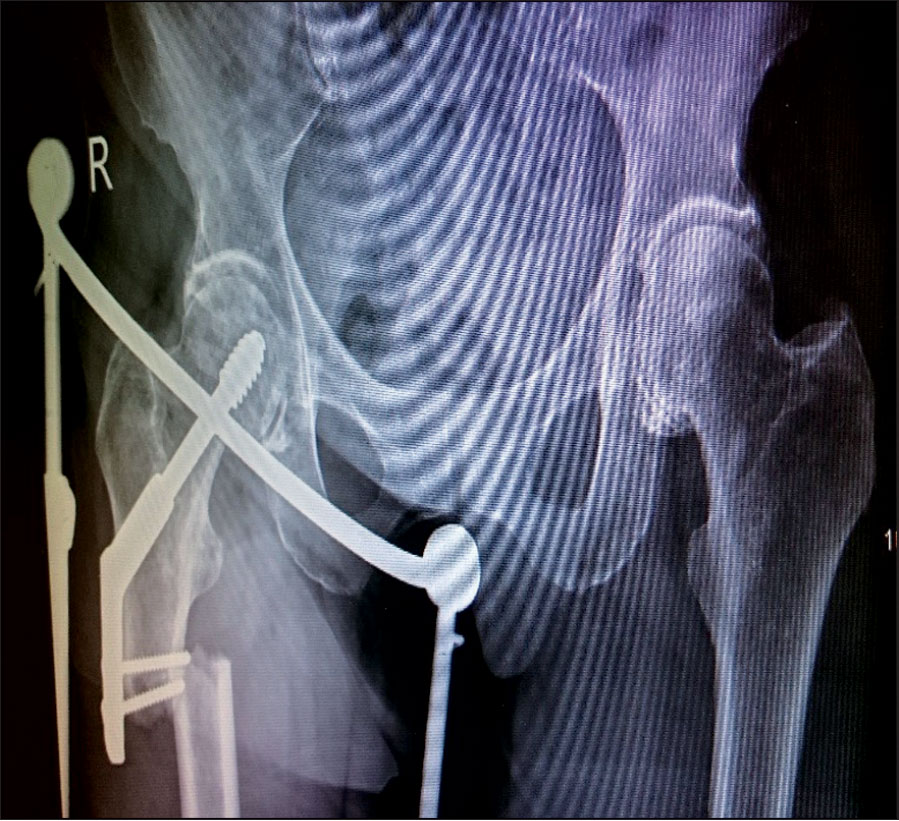

She was undergoing this treatment when in April 2015 she again had a low energy fall and was brought to hospital with pain right thigh and non-weight bearing. On x-ray she had DHS implant failure. She had the non-union of the original sub trochanteric fracture.

She was taken to theatre again and the DHS implant was removed. A long cephalomedullary nail was inserted. After that she was again started on physiotherapy.